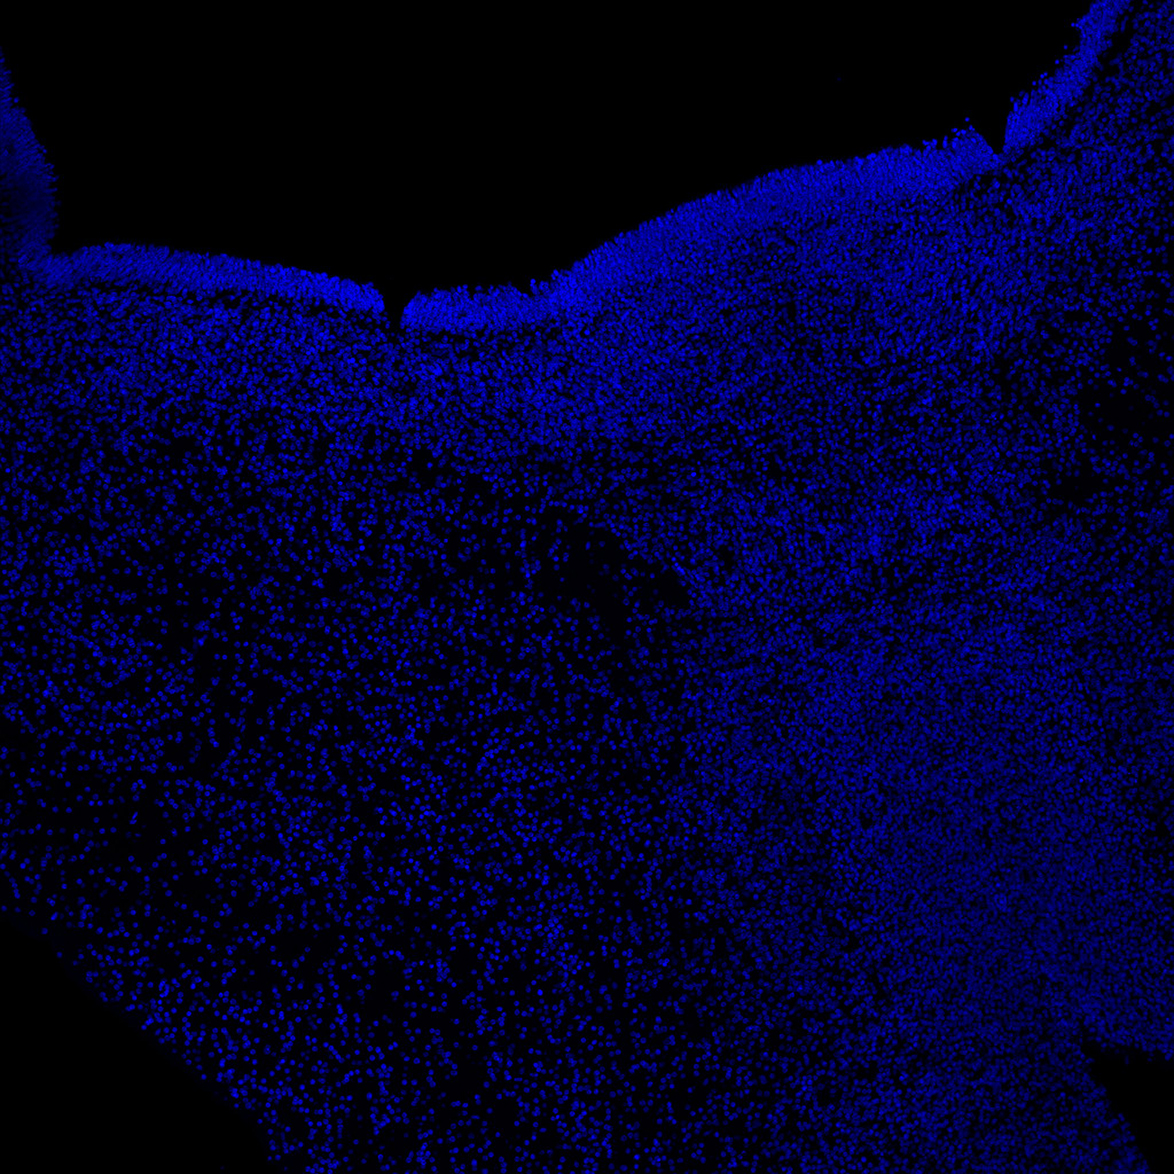

DAPI

6PCW human midbrain